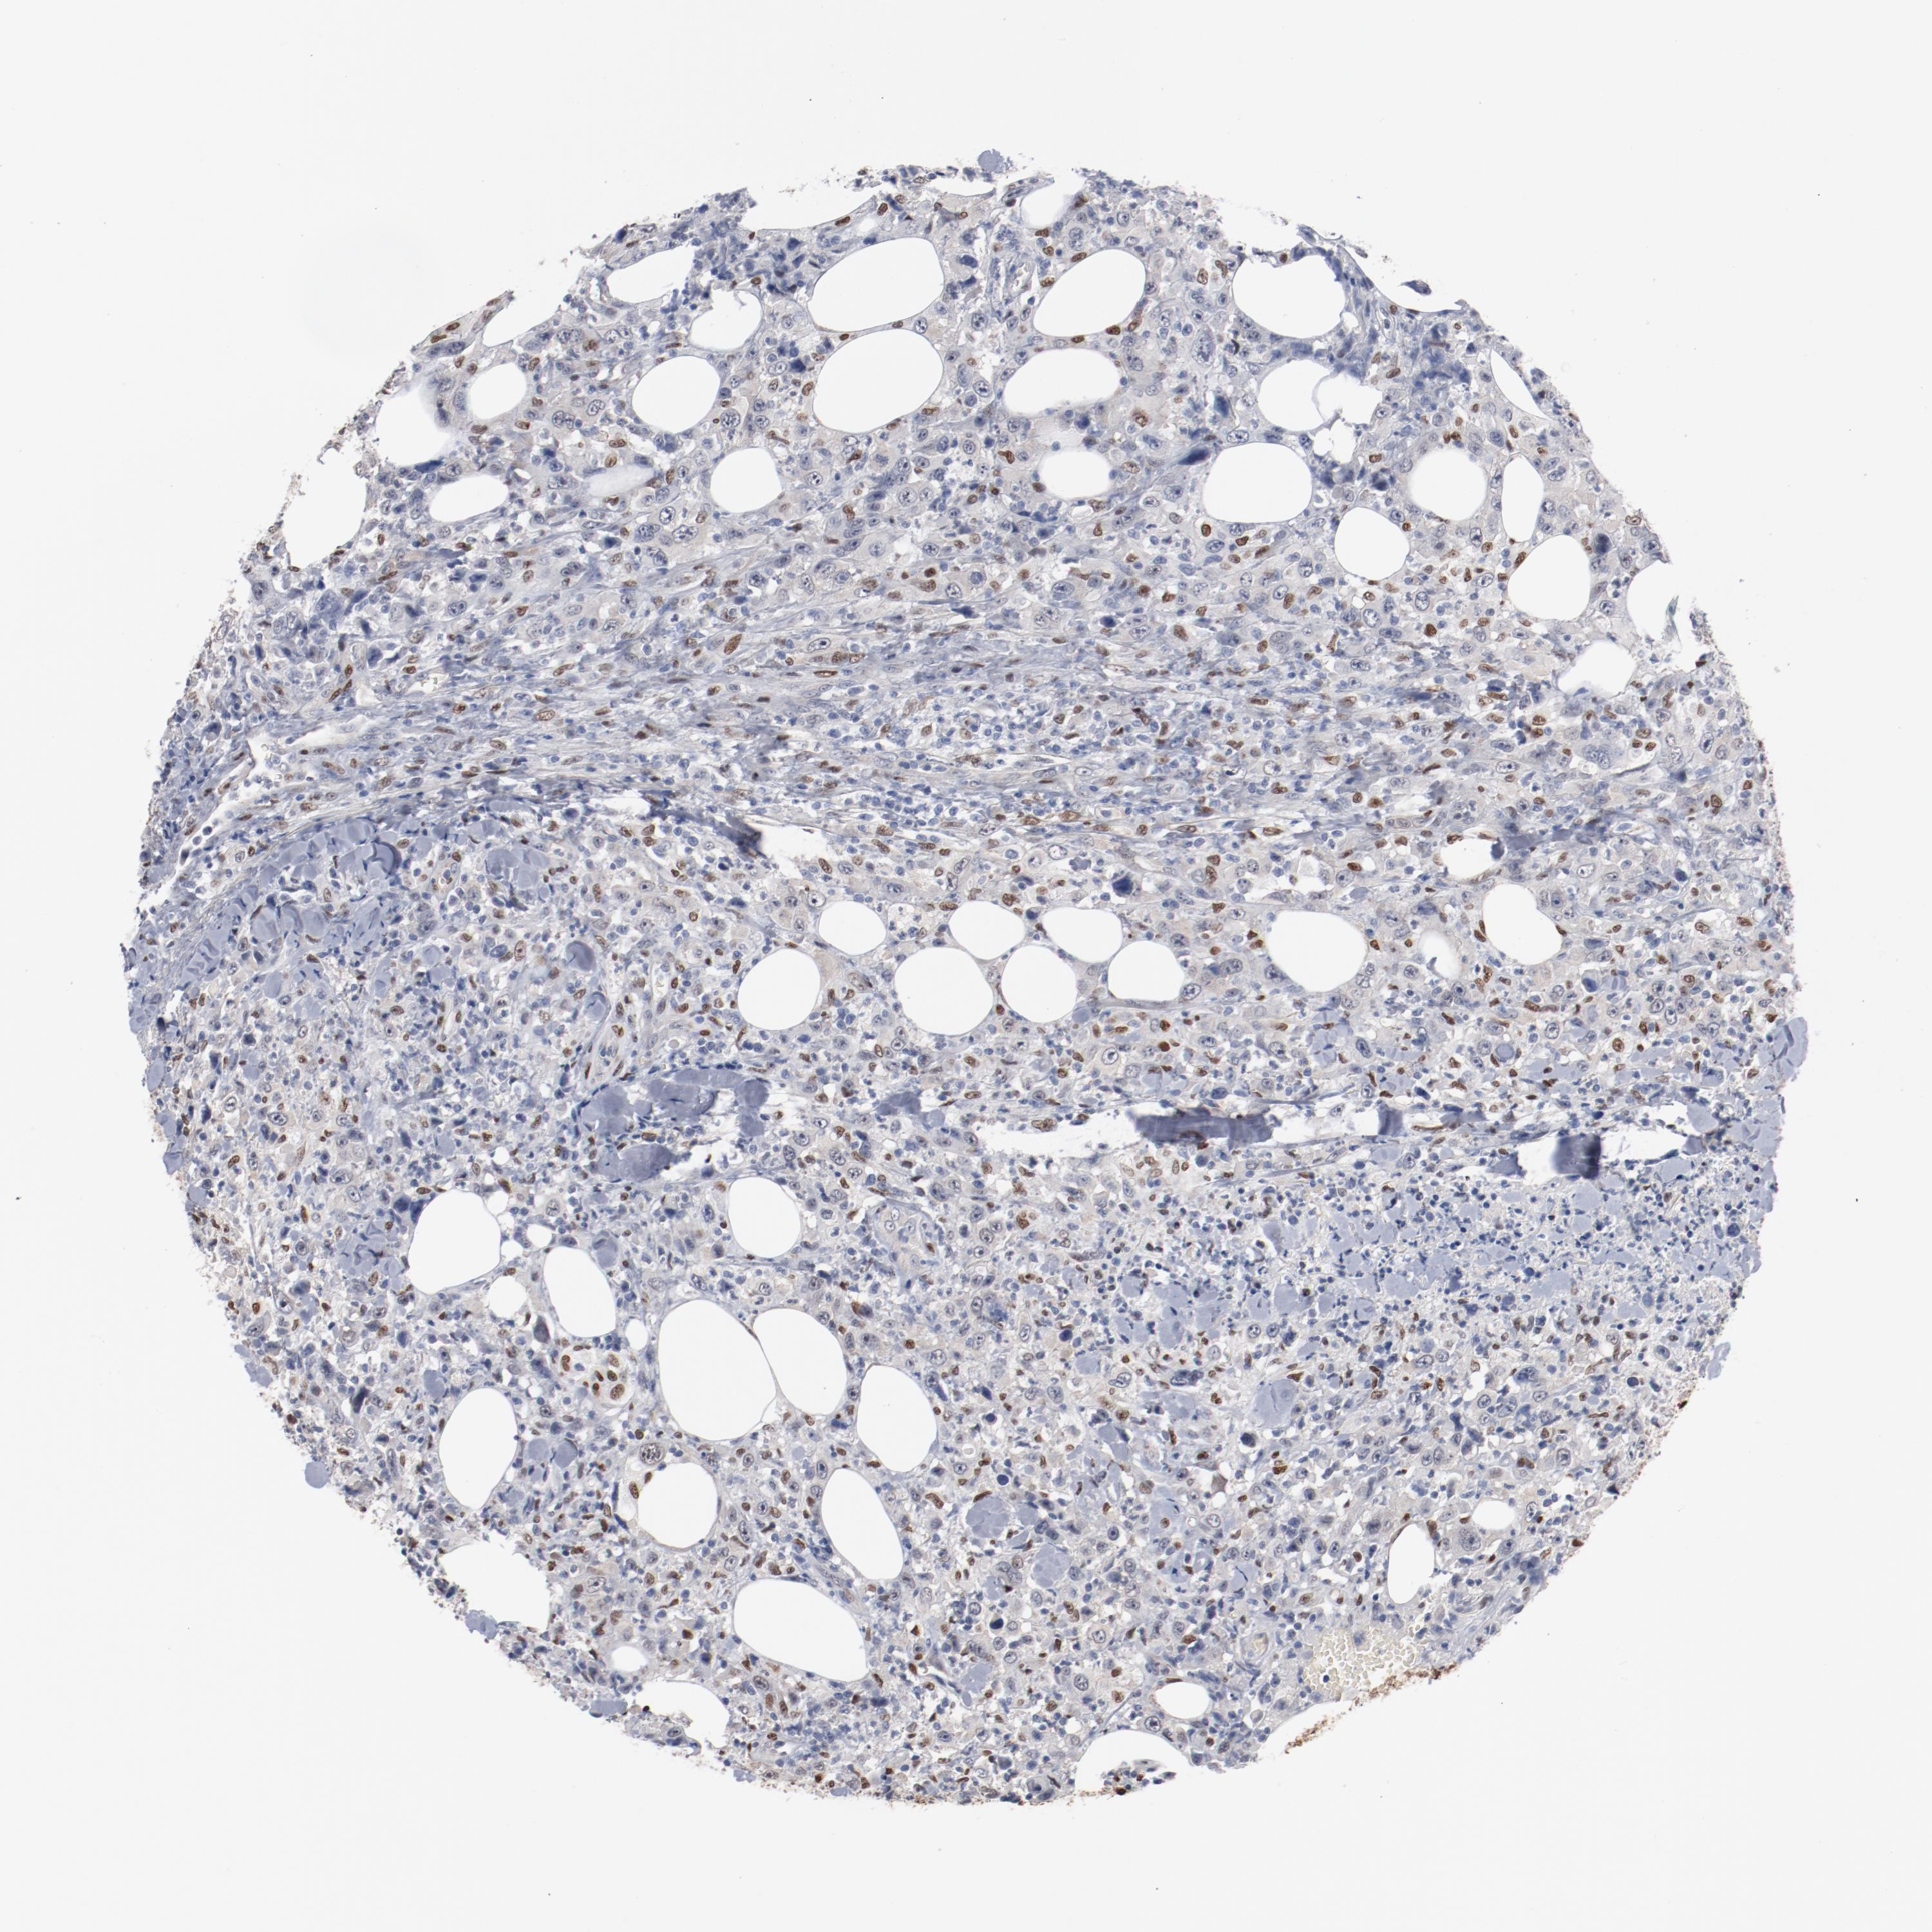

THYROID CANCER - Protein expressioni

A mouse-over function shows sample information and annotation data. Click on an image to view it in a full screen mode. Samples can be filtered based on level of antibody staining by selecting one or several of the following categories: high, medium, low and not detected. The assay and annotation is described here.

Note that samples used for immunohistochemistry by the Human Protein Atlas do not correspond to samples in the TCGA dataset.

Antibody stainingi

Antibody staining in the annotated cell types in the current human tissue is reported as not detected, low, medium, or high, based on conventional immunohistochemistry profiling in selected tissues. This score is based on the combination of the staining intensity and fraction of stained cells.

Each image is clickable and will lead to virtual microscopy that enables deeper exploration of all samples and also displays staining intensity scores, fraction scores and subcellular localization as well as patient and tissue information for each sample.

Antibody HPA003456

Staining

High

Medium

Low

Not detected

Intensity

Strong

Moderate

Weak

Negative

Quantity

>75%

75%-25%

<25%

None

Location

Nuclear

Cytoplasmic/membranous

Cytoplasmic/membranous,nuclear

Papillary adenocarcinoma, NOS

Carcinoma, NOS